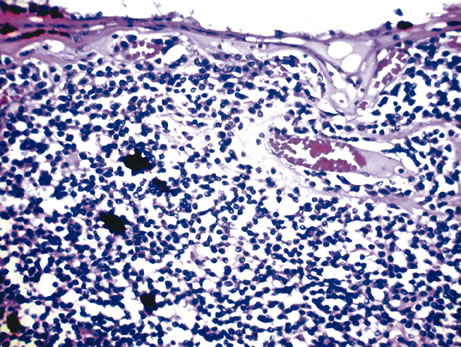

The pars plana and peripheral choroid can be involved with nongranulomatous chronic inflammatory infiltrate. Clinically, such inflammation is seen as vitritis and whitish exudative changes at the pars plana. When it is idiopathic, such inflammatory infiltrate may be termed pars planitis. A moderate to dense vitritis may be present. The vitreous inflammation may clump together and form “snow balls.” Typically, dense white material is present at the pars plana and posterior ciliary body; this is called a “snow bank.” Histologically, enucleated eyes with pars planitis reveal a lymphocytic infiltration in the pars plana and peripheral choroids (Fig. 10). The snow bank is made of fibroglial proliferation containing elements of ciliary epithelium, and vascular channels surrounded by mononuclear cells67–69 Features similar to pars planitis are also observed in patients with multiple sclerosis. Intermediate uveitis without a clear snow bank is seen in patients with sarcoidosis, Lyme disease, and intraocular inflammation associated with human T-cell lymphotropic virus type 1 (HTLV-1) infection.70–73

Fig. 10. Pars planitis. A. Peripheral choroid is infiltrated by lymphocytes. (Hemotoxylin-eosin ×35.) B. The “Snow bank” is made up of fibroglial cells and vascular channels lined by prominent endothelial cells ((×2000).